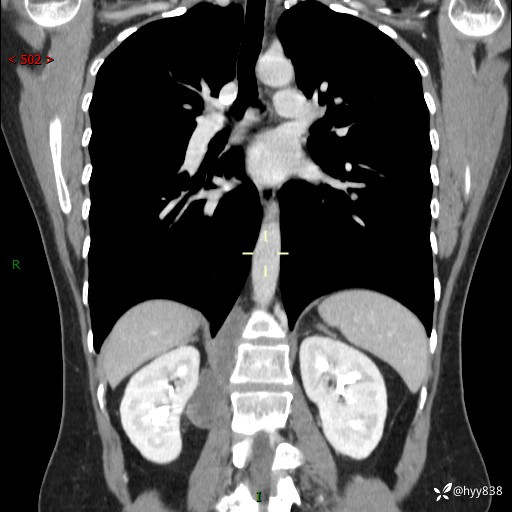

现在都流行跨界,病变也不例外,从腹膜后长到胸腔了---结果公布~

简要病史:患者于1天前因体检发现右旁肾占位,无肉眼血尿,无畏寒发热,无咳嗽咳痰,无腰腹部疼痛不适,无尿频尿急症状,起病来,患者未行特殊治疗,为求进一步诊治,门诊以"右侧腹膜后肿物"收治入院。 发病来患者精神、饮食、睡眠良好,小便如上,大便正常,体重无明显变化。

辅助检查:CT

临床诊断:腹膜后肿物

上腹部CT增强(动脉期+实质期)(外院平扫)